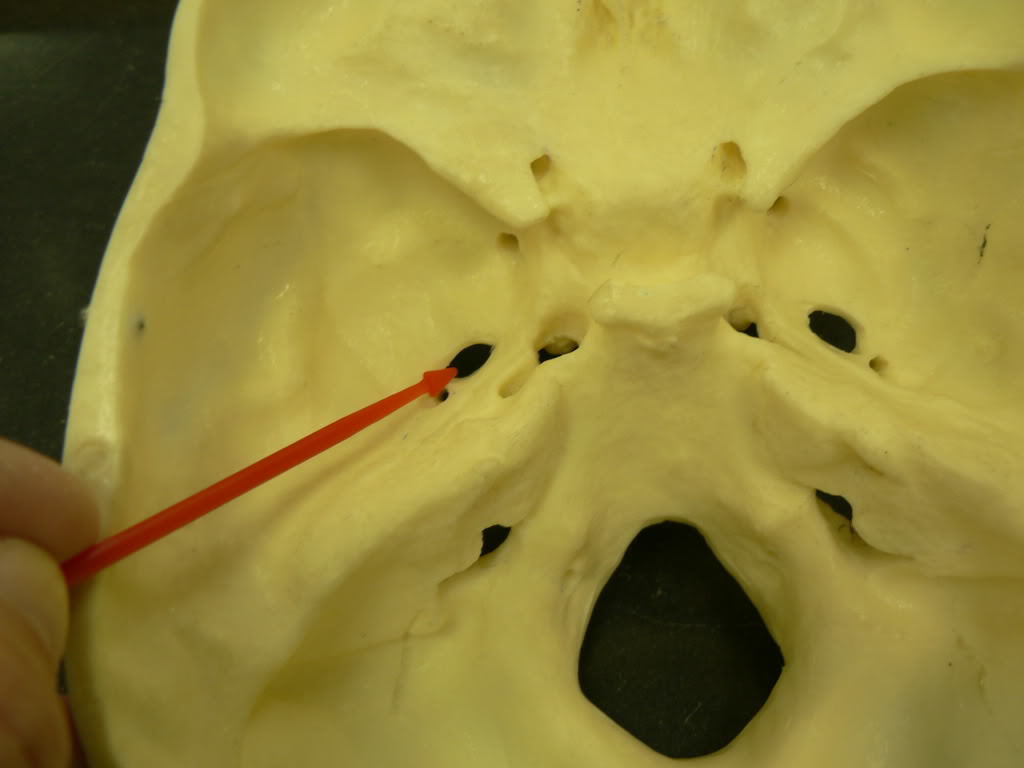

Jugular Foramen